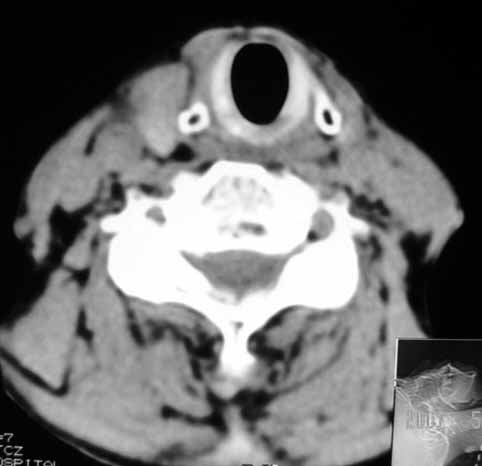

以下是引用jw-830在2007-5-24 15:33:00的发言:[br]右侧甲状腺增大,内可见低密度,病灶与周围软组织界线欠清晰,建议增强扫描除外甲状腺癌

以下是引用adams在2007-5-24 17:15:00的发言:[br]支持“ 右侧甲状腺增大,内可见低密度,病灶与周围软组织界线欠清晰,建议增强扫描除外甲状腺癌”。 [br] [br] [br][br] [br] [br]

以下是引用苯小孩在2007-5-24 15:26:00的发言:[br]左侧甲状腺腺癌或瘤,建议穿刺或核素进一步检查.